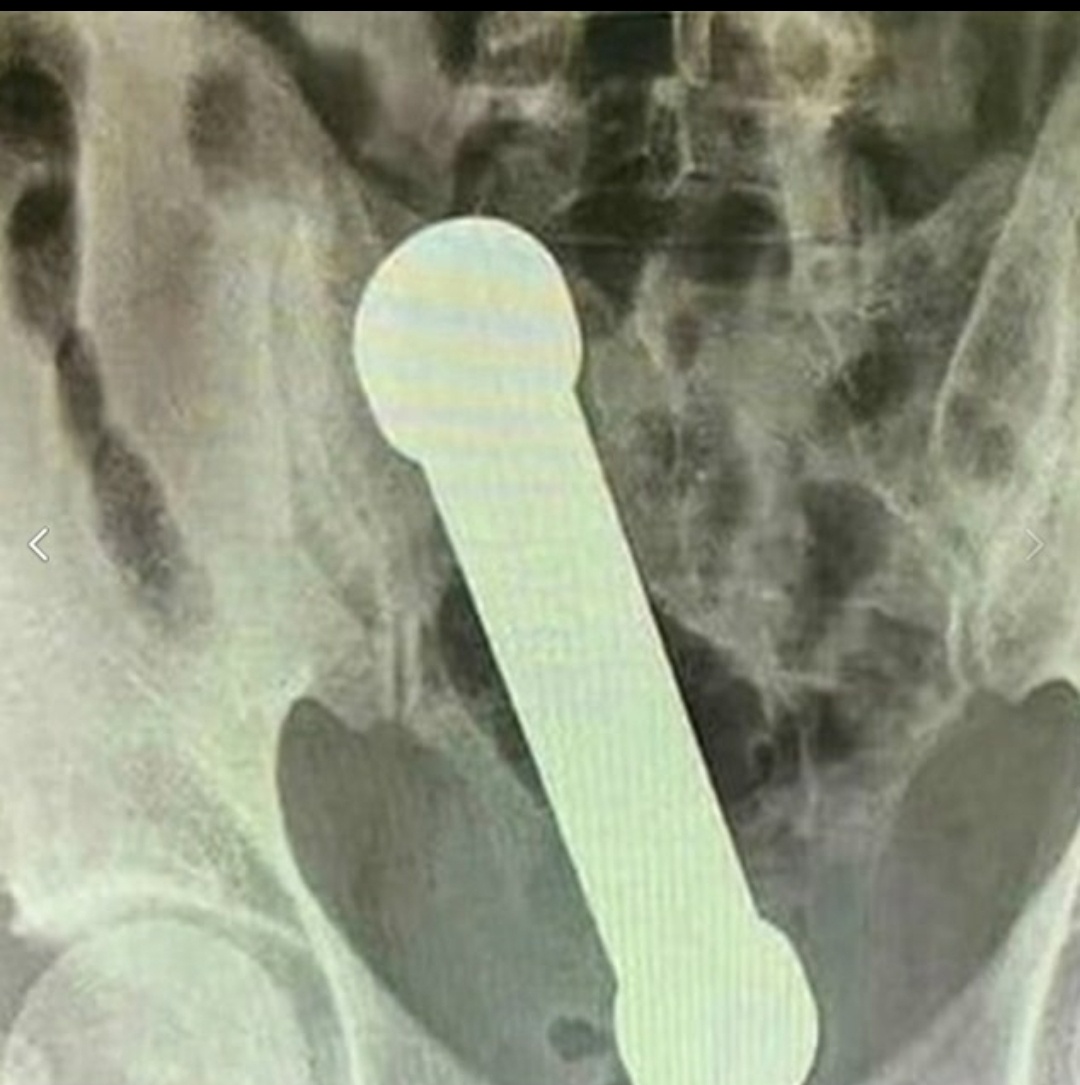

Наш герой (назовём его «энтузиаст нетрадиционного фитнеса») удивил медиков города N, явившись в клинику с необычной проблемой. А точнее — с гантелью весом 2 кг и длиной 20 см, которая решила погостить в его кишечнике. Не час и не два, а целых два дня. Видимо, он надеялся, что тело «привыкнет» и сделает гантель частью своего интерьера. Как вы думаете, что стало решающим фактором для визита к врачу? Осознание абсурдности ситуации или банальная проблема с посещением уборной, тошнота и дикая боль?

Приёмное отделение превратилось в филиал цирка, когда выяснилось, что извлечь «спортивный снаряд» обычными методами не удаётся. Пациенту дали успокоительное — не столько от боли, сколько от осознания масштаба курьёза. Но даже после этого медицинский пинцет оказался бессилен. Интересно, почему экспериментатор не додумался привязать к гантели верёвку для удобства извлечения? Вопрос, который, наверное, задали себе все присутствующие .

Кульминацией стал момент, когда человеку в белом халате с перчаткой на руке, пришлось буквально засучить рукав и… пройти вглубь пациента почти по локоть. Видимо, это новый тренд в мире здравниц и лечебниц: когда технологии бессильны, на помощь приходит старый добрый метод «ручной работы». Гантель засела намертво, будто решила прописаться там навсегда. Как вам такая перспектива — иметь личного «железного квартиранта»?